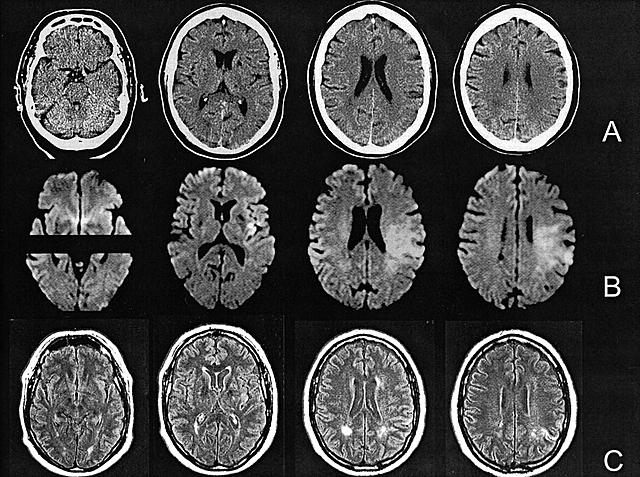

• First CAT scanner

First CAT scanner

This technology was developed by Godfrey Hounsfield and Allan Cormack and involves the combination of many X-ray images (with the help of a computer) for the purposes of generating cross-sectional views and 3D images. A revolutionary invention for microscropy!